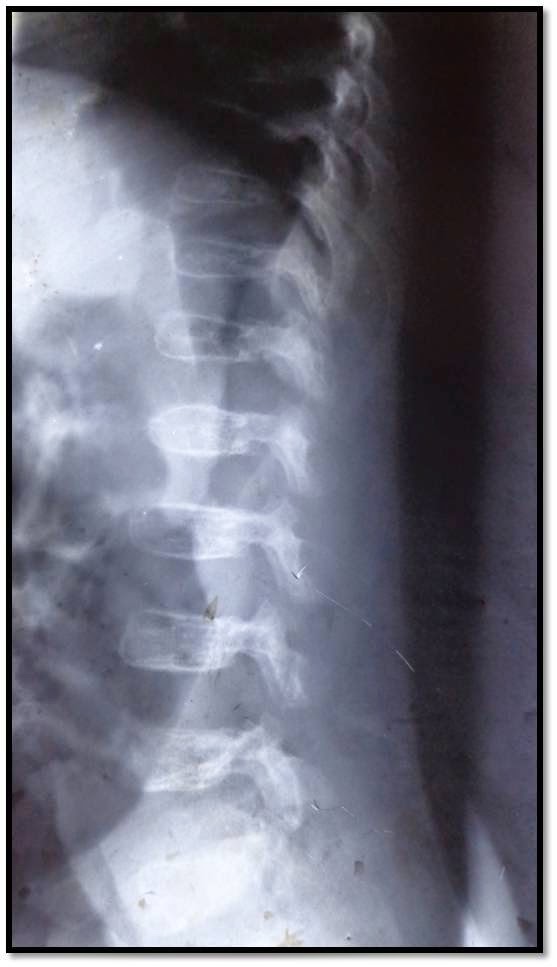

Gemeinsame Kennzeichen sind generalisierte Platyspondylie und Veränderungen der Metaphysen hauptsächlich an Hüft- und Kniegelenk.

- SMD Typ Kozlowski, autosomal-dominant vererbt, häufigste Form